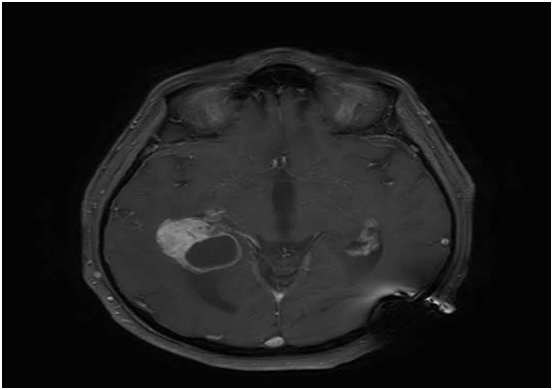

We report on an 72-year-old male patient with a history of treated RCC who presented after 40months with a classic but severe triad of Hakim and Adams (gait disturbance, urinary incontinence and cognitive dysfunction) due to hydrocephalus related to a choroid plexus mass in the trigonum of the both lateral ventricles (Figure 1). Because of the severity of symptoms we decided to first treat the symptoms of normal pressure hydrocephalus initially by external ventricle drainage and finally by VP-shunting to aim for fast symptomatic relieve. Follow-up imaging after 6weeks however showed clear disease progression unilateral in the right sided trigonum (Figure 2). Consequently the patient was referred to surgery to remove the right-sided lesion. The left-sided lesion was not resected. The histopathological examination was consisted with a RCC metastasis as the lesion had the characteristic clear-cell pattern immunoreactive to RCC and CD10 (Figure 3). The patient was referred to the medical oncologist for additional systemic treatment with tyrosine kinase inhibitors.

Figure 1 MRimage (T1 sequence) showing a bilateral (right >left) choroid plexus mass.

Figure 2 MR image (T1 sequence) demonstrating disease progression.